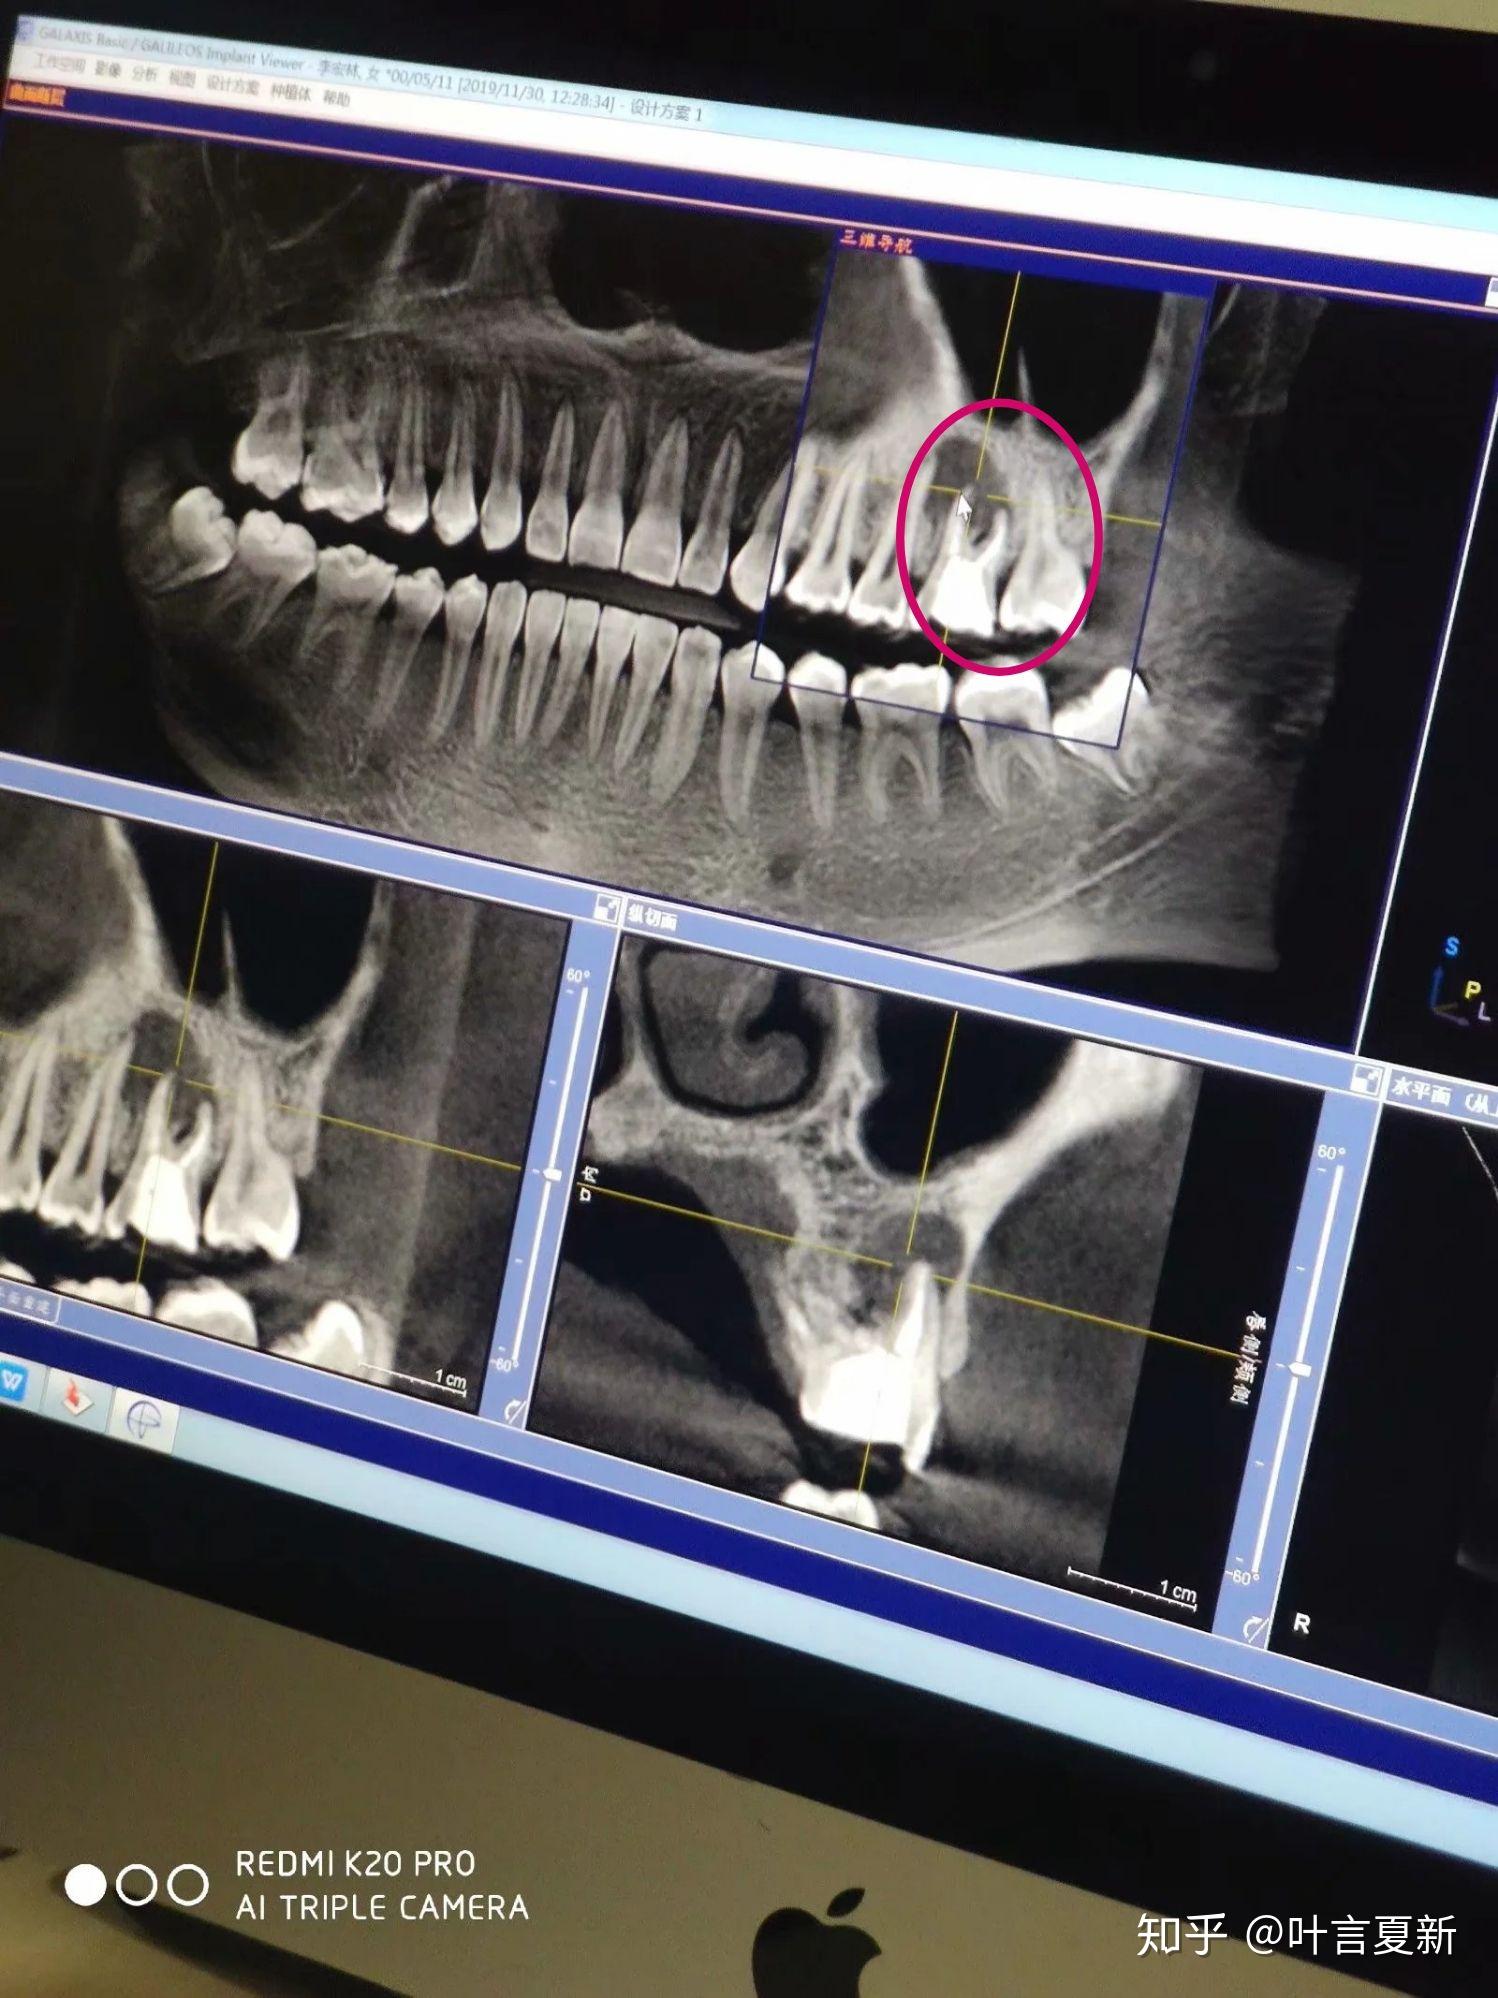

我的牙齿片子已经拍了,医生说有一个大的囊肿,请教,怎么办? - 知乎

图片尺寸1498x1998